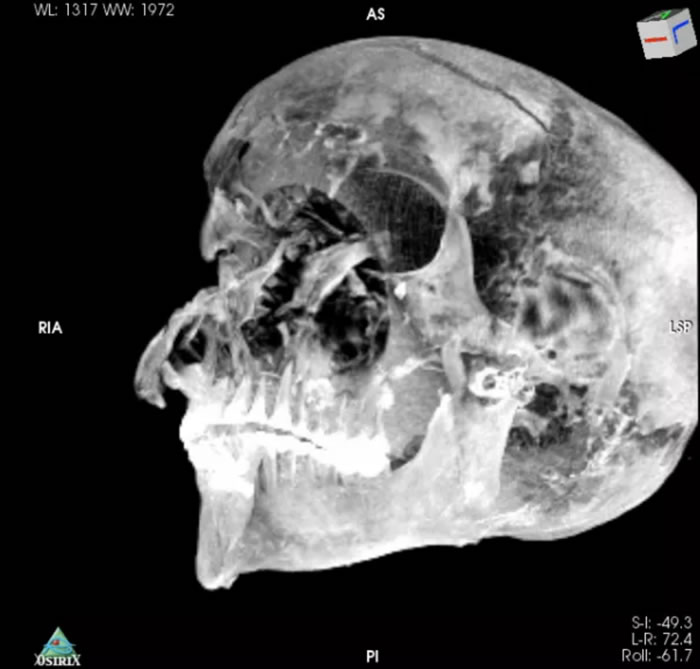

考古学家扎希·哈瓦斯与开罗大学医学院教授萨哈尔·萨利姆17日发表在期刊《医学前沿》上的研究成果显示,通过对木乃伊进行CT扫描并重建二维、三维图像,这两位学者发现,塞格嫩拉双手变形,头部伤痕被木乃伊制作者隐藏在一种防腐材料下,这些伤痕与埃及国家博物馆现存的希克索斯人使用的斧头、匕首等相吻合。

因为CT图像显示,法老王的头部左侧有另一组伤痕,但古代的防腐工匠巧妙地掩饰了Sequnenre的遗容,以至于1960年代的X光照都没能意识到这一点。